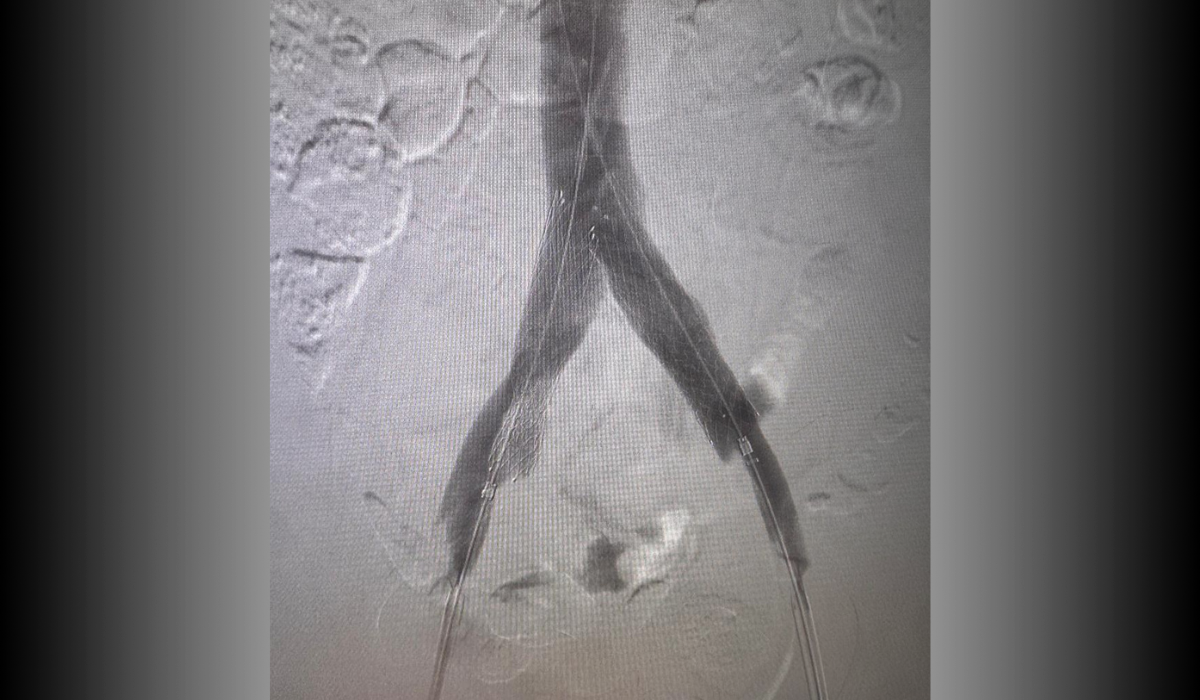

Pre-treatment: Bilateral iliac vein occlusion

Pre-treatment

Bilateral iliac vein occlusion associated with pelvic congestion syndrome.